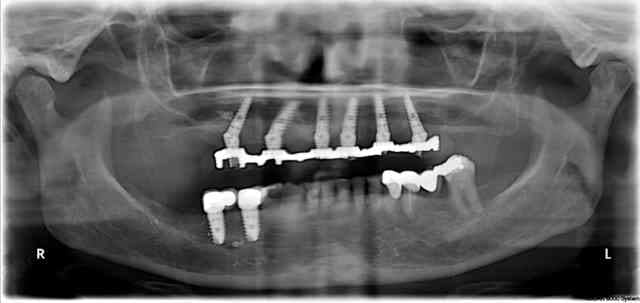

D’après cette pano, extraction implantation MCI ?

Un mini implant a était retiré aisément par dévisage...

Pano de contrôle